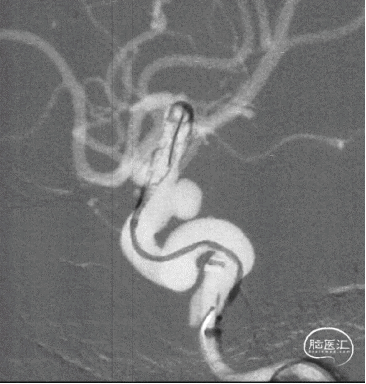

现病史:患者因头痛17天,外院行头颅CTA提示:左侧颈内动脉交通段动脉瘤,动脉瘤大小约5.3×5.4mm,形态不规则,左侧大脑前动脉A1段瘤样凸起。

初步诊断:左侧颈内动脉交通段动脉瘤。

头颅CTA

可见一小泡自动脉瘤瘤体上发出

瘤体最大径6.92mm

远端血管直径:3.28mm

近端血管直径:3.98mm

同侧A1可见一小瘤突起